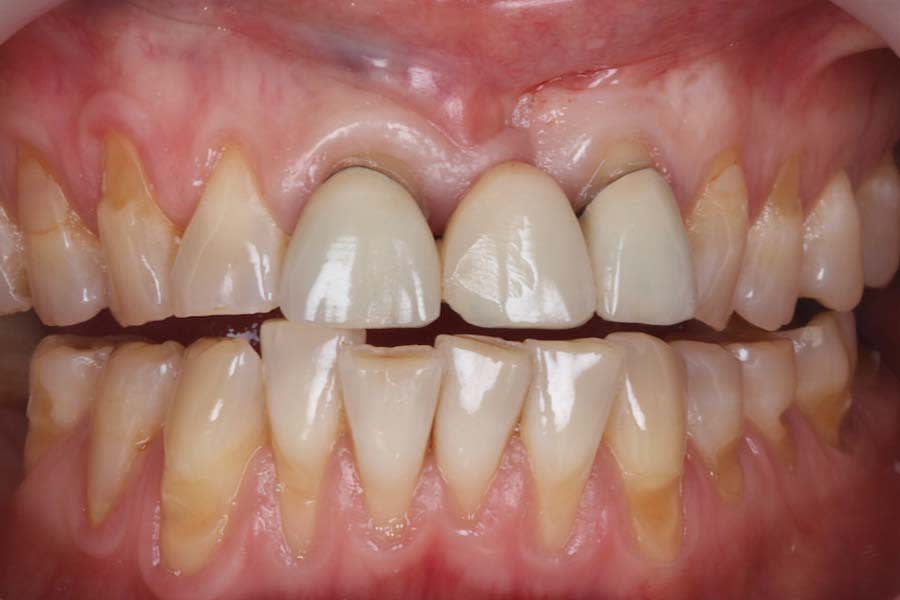

A 47-year-old female patient presented to the prosthodontics clinic at the University of Pennsylvania School of Dental Medicine with severe dental wear. Her chief complaint was that she didn’t like the appearance of her “front teeth” and was very concerned about her teeth “breaking apart” (Figure 1 and Figure 2). She reported noticing metal exposure on the existing fixed dental prosthesis (FDP) at Nos. 8 through 10 and progressive tooth wear. Her condition was causing her significant anxiety, which had worsened during a recent period of emotional stress accompanied by increased clenching. A recent tooth chipping incident with associated hypersensitivity of tooth No. 18 prompted her to seek definitive care.

Intraoral and extraoral photographs and digital scans were obtained. Bite registration was taken in centric relation, along with three additional registrations at 1 mm, 1.5 mm, and 2 mm increased OVD using a leaf gauge. Medical and dietary history revealed mild gastric reflux and habitual tea consumption. Clinical examination identified multifactorial wear, with signs of intrinsic and extrinsic erosion, attrition, and abrasion (Figure 3 and Figure 4). There was significant tooth structure loss and partial dentoalveolar compensation. The gingival phenotype was thin, with RT1 recession defects at multiple sites.27

The patient expressed satisfaction with the final esthetic outcome (Figure 15). An occlusal appliance was fabricated and delivered, and preventive strategies and maintenance protocols were reinforced with the patient. She was advised to maintain regular dental recall and topical fluoride varnish application. With compliance to these recommendations, a favorable long-term prognosis is anticipated.